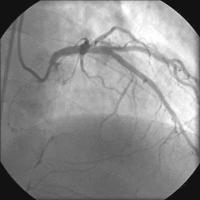

Kontrollangiographie

Abbildung 14: Kontrollangiographie nach 3 Monaten - RAO/kranial

Abbildung 15: Kontrollangiographie nach 3 Monaten - LAO/kaudal.